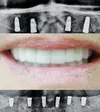

Zirkonyum uygulamalar

Implant tedavisi

Porselen uygulamaları

Laminate veneer